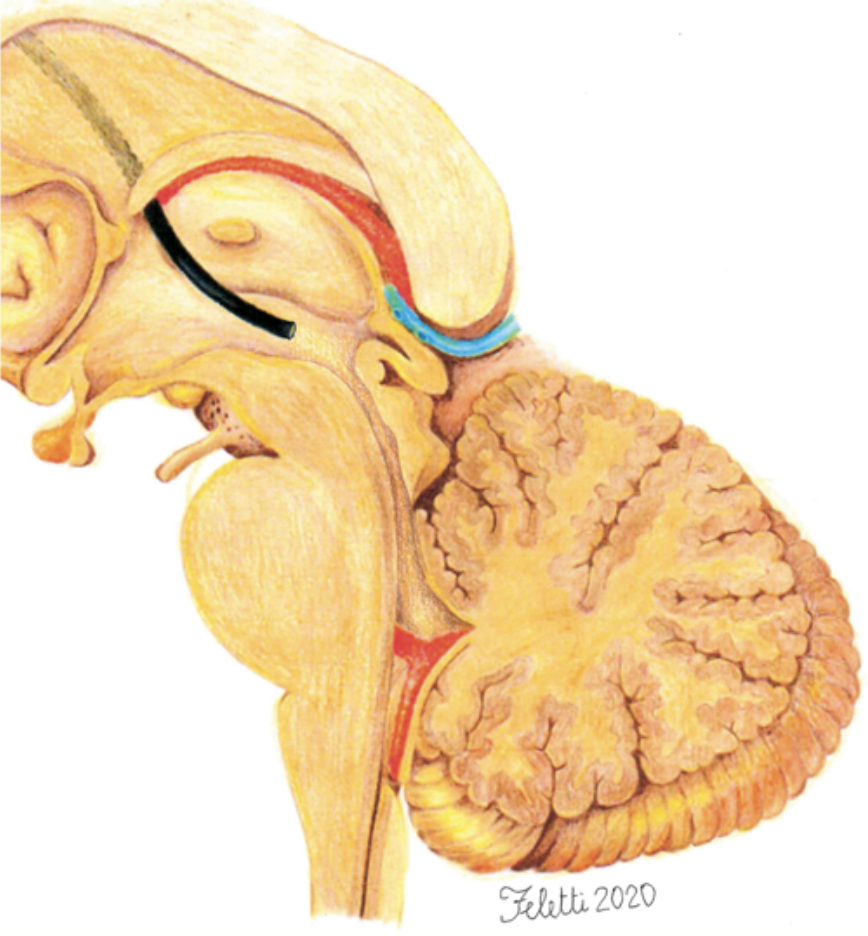

Neurochirurgo presso l'Azienda Ospedaliero-Universitaria Integrata di Verona, ha eseguito circa 3.000 interventi neurochirurgici, di cui oltre 2.000 come primo operatore. Affianca all'attività clinica un impegno costante nella ricerca e nella didattica universitaria. È autore di oltre 100 pubblicazioni peer-reviewed e 10 capitoli di libro, illustratore anatomico per pubblicazioni scientifiche ed Associate Editor di Frontiers in Surgery — Neurosurgery. Ha maturato esperienze di ricerca e cliniche all'estero, tra cui l'Università della California a San Francisco (UCSF), la Fujita Health University (Nagoya) e la Fudan University (Shanghai).

I suoi interessi chirurgici principali comprendono la chirurgia vertebrale, la chirurgia cerebrovascolare, i tumori cerebrali, i tumori intramidollari, la neuroendoscopia e la neurochirurgia funzionale. È inoltre titolare di un brevetto per un elettrodo di neuromonitoraggio in ambito endoscopico (brevetto italiano ed europeo).